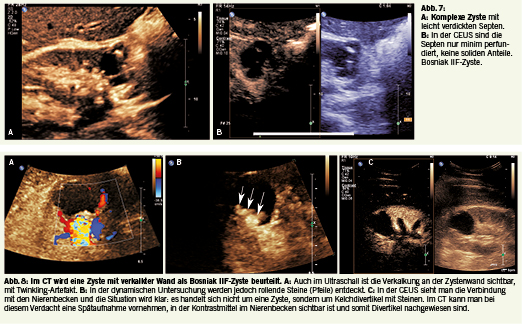

Charakteristika Bosniak IIF komplexe Zyste

• Wand teils leicht verdickt (2-3 mm) und oder

verkalkt

• Septen viele, <2 mm dünn, kaum perfundiert,

2-3 mm dick

• Zysteninhalt echofrei oder homogen oder gemischt echogen

• Kontrastierung minim

• Solide Anteile keine

Die Bosniak IIF-Zysten wurden früher der Kategorie III zugeordnet und die meisten Fälle waren benigne. In der Folge hat man eine neue Kategorie IIF gebildet, wobei «f» für «follow» steht. Bei dieser Bezeichnung ist eine Nachkontrolle in 6 Monaten angezeigt (Abb. 7a-b). In der CT-Untersuchung hat man eine Veränderung als Zyste IIF beurteilt, mit knotiger Verkalkung der Wand. Diese Veränderung hat man auch im Ultraschall gesehen, die dynamische Untersuchung zeigt jedoch rollende Steine und in der Spätaufnahme mittels CECT konnte man klar den vermuteten Kelchdivertikel mit Steinen diagnostizieren (Abb. 8 a-c).